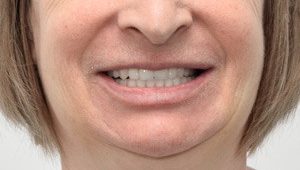

Омоложение без пластики и филлеров – поставьте импланты и станьте на 10 лет моложе!

- Поддержать мышцы лица в тонусе

- Избавиться от морщин

Через 5 лет ношения съемных протезов

После имплантации All-on-4